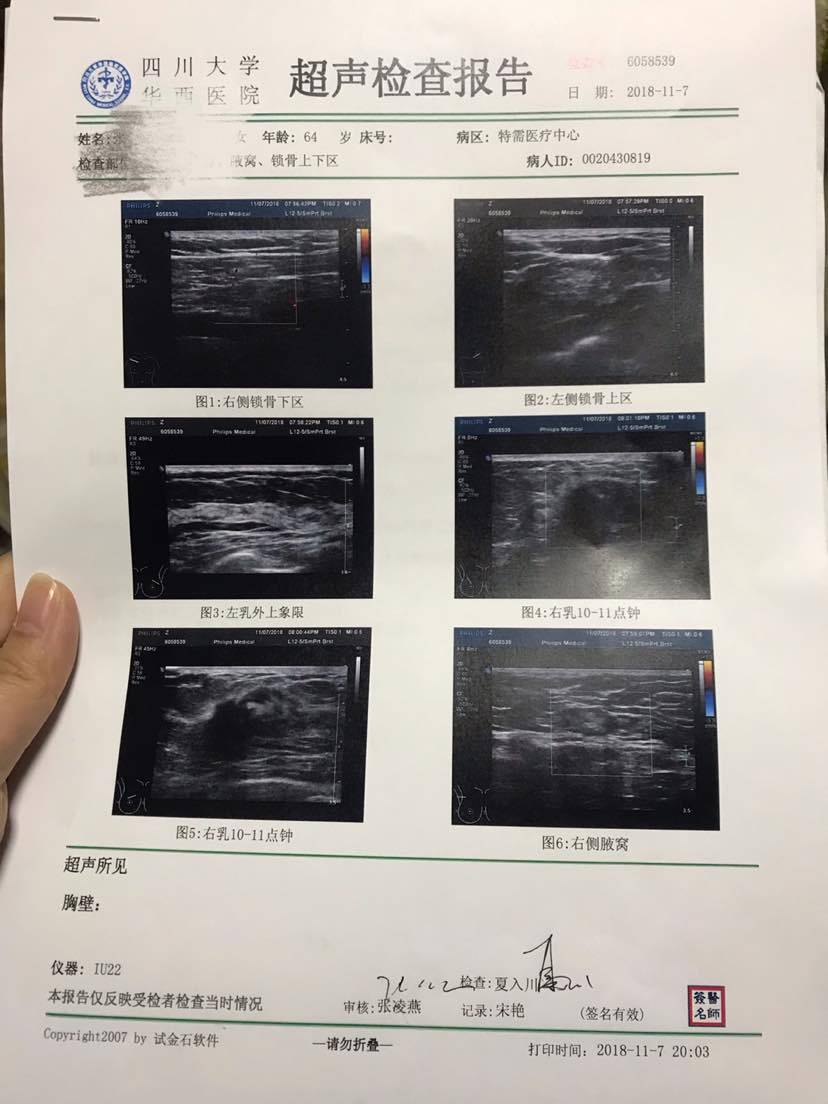

第二家的。有懂的朋友吗?我们也做了最坏的打算,会和我妈妈一起努力的!

我妈妈,64岁。平时乐观开朗,就是脾气有点急。前两天说乳房痛,牵扯到后背也有痛。看我们忙,都痛了好几天才说。找了最近的第一人民医院做检查。结果出来医生立马然后住院,化疗,手术。我都蒙了,太突然了,可是我觉得活检都没有做,不放心。第二天一早在华西挂了个特需号。抽了血,做了彩超,做彩超的时候那个医生说我妈妈情况不太好,说好久没遇到这种情况。今天又去见了医生,说还是要看活检结果,如果是癌就是有转移了。预约的周一做活检,乳房和锁骨两处的活检。好希望好希望我妈妈能好起来!